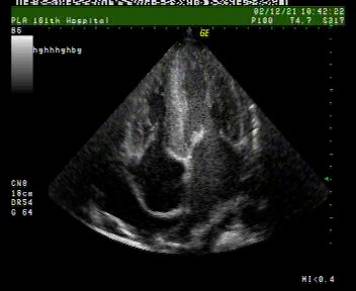

超声心动图:

◆室壁增厚,小心室腔,心房扩张以及左心室功能不全征象

◆心包积液也很普遍

◆2维超声可见心室肌中闪耀的颗粒状结构,可能是因为含有淀粉